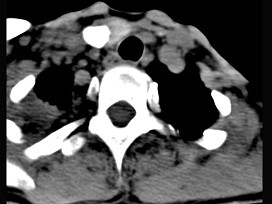

20.50岁女性患者,体检发现右侧甲状腺有较硬结节,CT扫描如图所示,请选择正确的描述和答案  (    )

正确答案:ABE